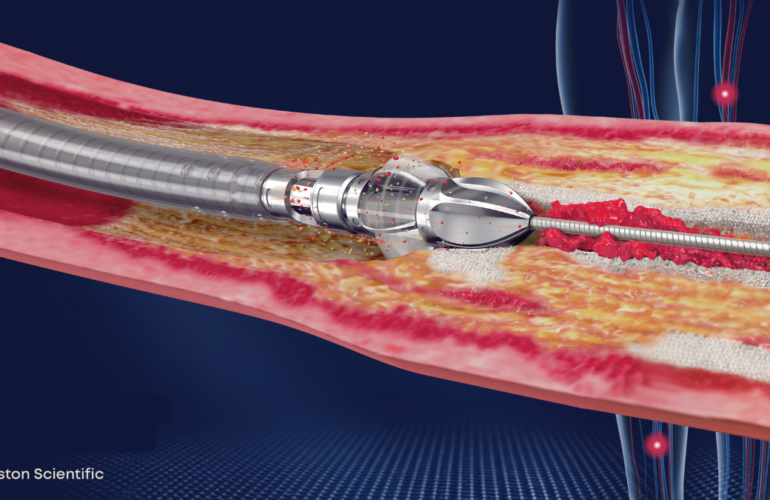

Jetstream atherectomy: A cutting-edge solution for arterial blockages

Jetstream atherectomy is a cutting-edge, minimally invasive procedure that effectively removes arter…